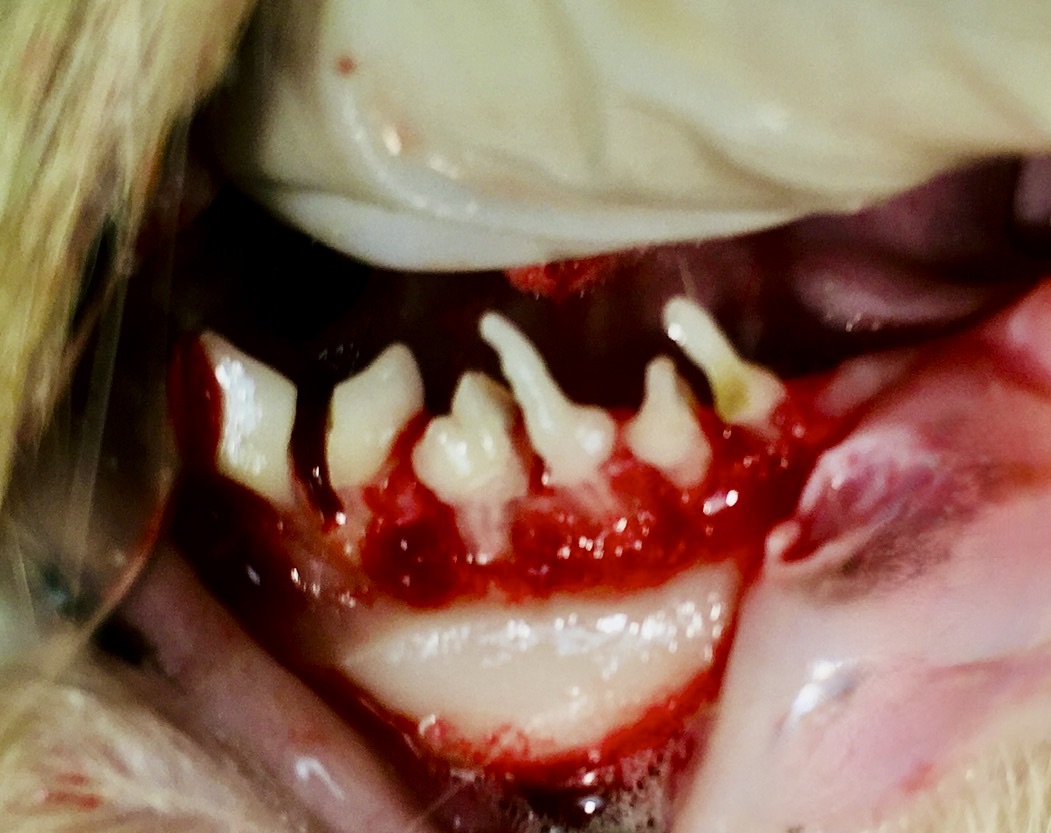

Donc… pour résumer, on va d’abord détacher la gencive de la dent, exposant ainsi l’os de la mâchoire (os alvéolaire). Celui-ci est abrasé avec une fraise sur la face externe de la dent, (on parle d’ostéotomie alvéolaire), ce qui a pour effet d’amoindrir l’ancrage des racines, vu qu’elles ne tiennent plus à l’os que par un seul côté : elles seront donc plus faciles à « luxer » pour les détacher. Les dents à plusieurs racines étant difficiles à retirer, on les découpe à la fraise en plusieurs fragments, chacun avec une seule racine : on parle de séparation radiculaire. Tout cela est en images ci-dessous.

Photo de gauche : l’os alvéolaire a été abrasé, les racines ne sont plus ancrées que d’un seul côté, et seront plus faciles à détacher, avec moins de risque qu’elles se cassent ; et si cela arrive malgré tout, le morceau cassé sera facile à repérer et à retirer ! A droite : toutes ces dents étaient à racine double et ont été découpées afin que chaque morceau ne soit plus relié qu’à une seule racine, plus facile à retirer intacte.